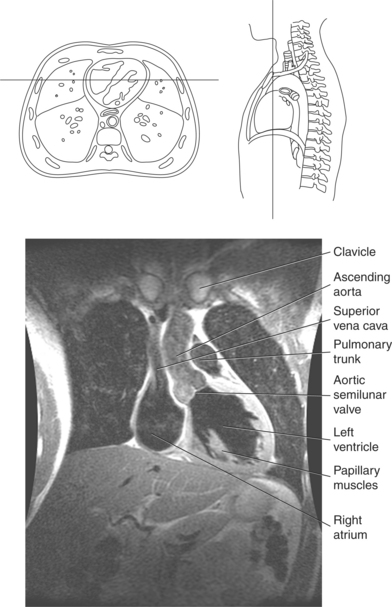

The right atrium forms the right border of the heart and receives deoxygenated blood from the body via the superior and inferior venae cavae and from the coronary sinus and cardiac veins that drain the myocardium. A small muscular embryonic appendage, the right auricle, projects upward and toward the left from the right atrium, covering the root of the aorta (Figure 6.40). The right ventricle lies on the diaphragm and comprises the largest portion of the anterior surface of the heart. It receives deoxygenated blood from the right atrium and forces it into the pulmonary trunk for conveyance to the lungs. Projecting off the inferior surface of the ventricular walls are conical-shaped projections of cardiac muscle called papillary muscles that anchor the cusps of the tricuspid valve to the right ventricle (Figure 6.39). The left atrium lies posterior to the right atrium and is the most posterior surface of the heart. It also has an embryonic appendage, the left auricle, that projects to the left of the pulmonary trunk over the superior surface of the heart. The left atrium receives oxygenated blood directly from the lungs via the four pulmonary veins (two on each side). The left ventricle forms the apex, left border, and most of the inferior surface of the heart. It receives oxygenated blood from the left atrium and pumps it into the aorta for distribution throughout the systemic circuit. The myocardium of the left ventricle is normally three times thicker than that of the right ventricle, reflecting the force necessary to pump blood to the distant sites of the systemic circulation (Figures 6.41 through 6.52). Two papillary muscles project from the ventricular walls to anchor the bicuspid valve to the ventricle (Figures 6.39 and 6.47).

The semilunar valves are located at the junction where the ventricles meet the great vessels, separating the ventricles from the circulatory system. These valves are called semilunar because of their three crescent-shaped cusps and function to prevent the flow of blood back into the ventricles during ventricular relaxation. The pulmonary semilunar valve is located at the juncture of the right ventricle and pulmonary artery, and the aortic semilunar valve lies between the left ventricle and ascending aorta (Figure 6.51 through 6.53).